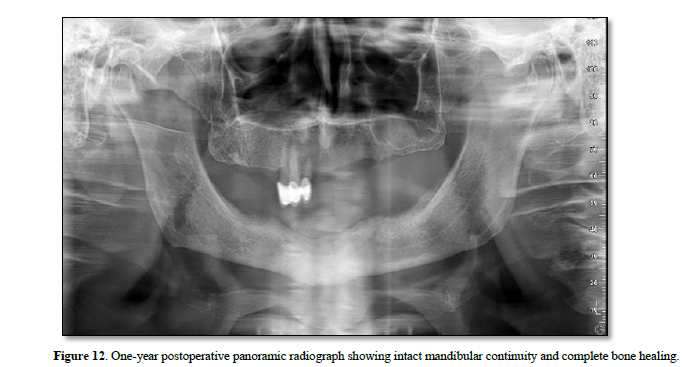

At the one‑year follow‑up, intraoral examination showed complete mucosal healing (Figure 11). CBCT acquired at the same visit—axial, sagittal, and frontal views plus three‑dimensional reconstruction—demonstrated stable bone remodeling of the anterior mandible (Figures 5–8). A one-year postoperative panoramic radiograph also confirmed preserved mandibular continuity, absence of recurrent pathology, and satisfactory bone healing (Figure 12).